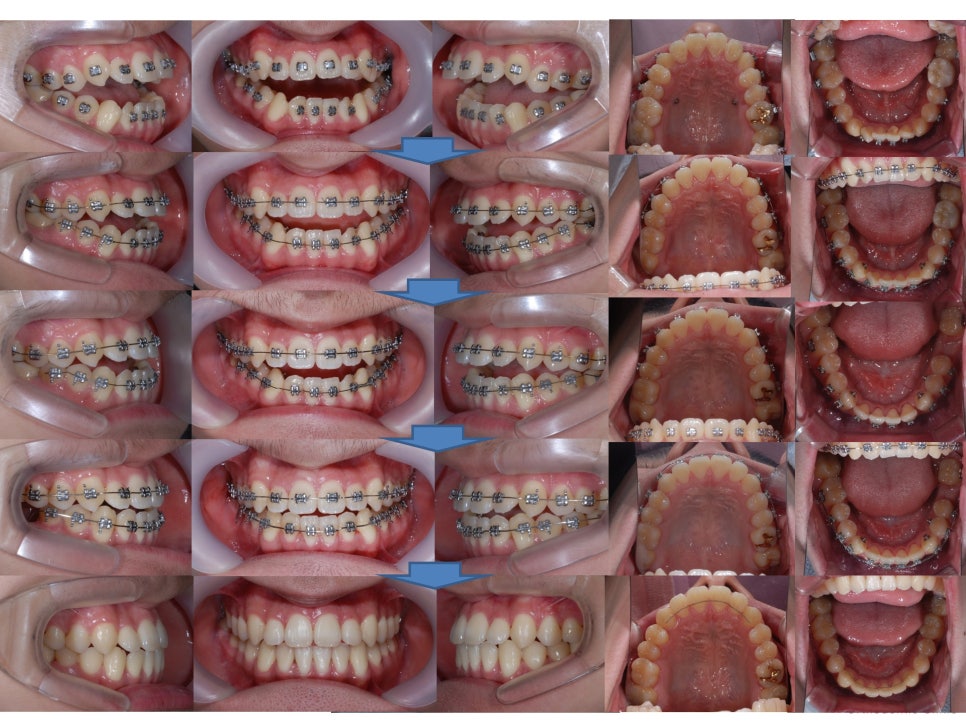

°³¹æ±³ÇÕÀÌ ¸¹ÀÌ °³¼±µÈ °ÍÀ» º¼ ¼ö ÀÖ½À´Ï´Ù.

µåµð¾î ¹ßÄ¡Çß´ø ¾î±Ý´Ï °ø°£µµ

´Ù ¾ø¾îÁö°í

¾È¸éºñ´ëĪ Ä¡¾Æ±³Á¤+

°³¹æ±³ÇÕ Ä¡¾Æ±³Á¤ÀÌ

Àß ¸¶¹«¸®µÈ °ÍÀ» º¼ ¼ö ÀÖ½À´Ï´Ù.

Àü¹ÝÀûÀÎ

ºñ¼ö¼ú ¾È¸éºñ´ëĪ Ä¡¾Æ±³Á¤

ºñ¼ö¼ú °³¹æ±³ÇÕ Ä¡¾Æ±³Á¤

Ä¡·á°úÁ¤ÀÔ´Ï´Ù.

¾î±Ý´Ï¸¦ ¹ßÄ¡ÇÏ¿´°í

»ç¶û´Ï°¡ ¾ÆÁ÷ ¸Ó¸® ¹Û¿¡

Çü¼ºÀÌ ¾ÈµÈ »óÅ¿´Áö¸¸

»Ñ¸®°¡ Àß ¹ßÀ°µÇ¸é¼­

Á¤»óÀûÀ¸·Î

¾î±Ý´Ï ¿ªÇÒÀ» ÇÒ ¼ö ÀÖ°Ô µÈ °ÍÀ» º¼ ¼ö ÀÖ½À´Ï´Ù.